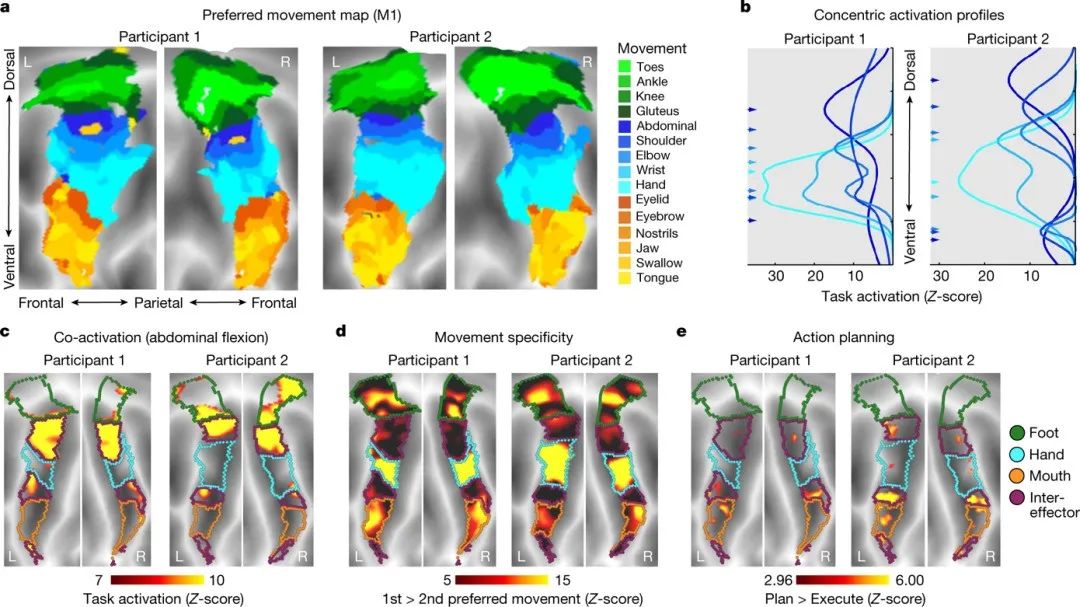

为了理解效应物之间的功能,作者对两位参与者进行fMRI深度数据收集,包括在25种不同运动表现期间以及新事件任务期间协调手脚运动的阶段。作者发现效应物特定区域的运动地形更符合concentric organization(图3a)。

同时,通过拟合高斯曲线来正式测试concentric organization,发现concentric activation zones的中心位于远端运动(图3b),向外扩展到近端运动。效应物之间表现出较弱的运动特异性,但在大多数运动中至少观察到一些激活。

在行动计划期间,效应物之间表现出比运动执行更大的活动,这表明行动计划的实施可能有一部分是由M1中的效应物之间的区域实现的(图3e)。

图3. M1中特定于个人的任务激活